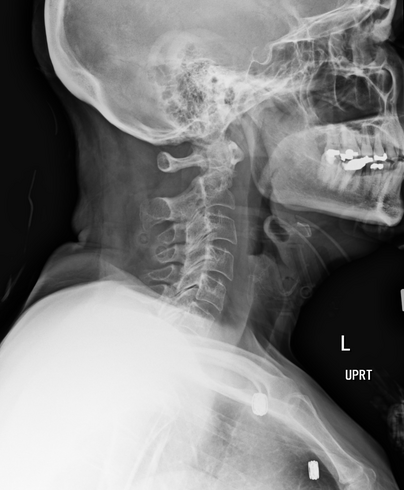

Evaluate the Lateral C-spine radiograph below and select any of the statements that are true (multiple answers possible):

All required vertebrae are demonstrated

A repeat with more flexion of the head/neck is needed

The R/L marker is correct

This is a well-positioned radiograph; no repeat required.

3 only